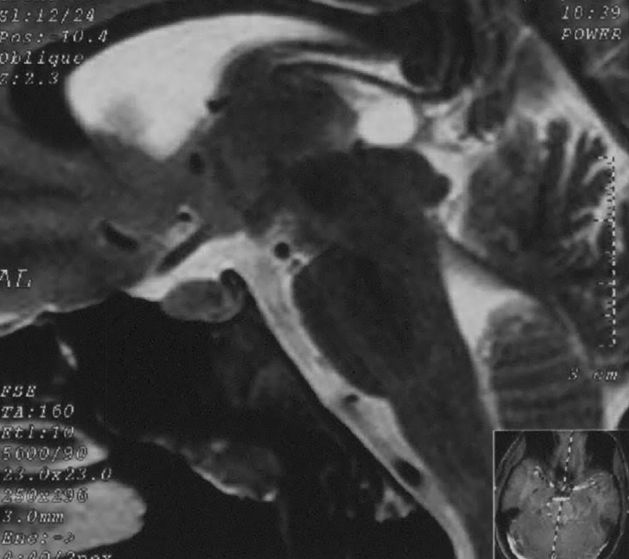

松果体区肿瘤的症状可以随其不同的组织学而不同。出现颅内压升高症状和体征的患者需接受头部CT扫描或MRI检查,以评估紧急处理的必要性。松果体区肿瘤患者的后续非急诊检查可分...

多形性胶质母细胞瘤(GBM)很少在松果体区发现。本文介绍了一个松果体区原发性胶质母细胞瘤(GBM)的病例,讨论了临床过程、影像学表现和治疗方法。根据先前描述松果体区GBMs软脑膜...